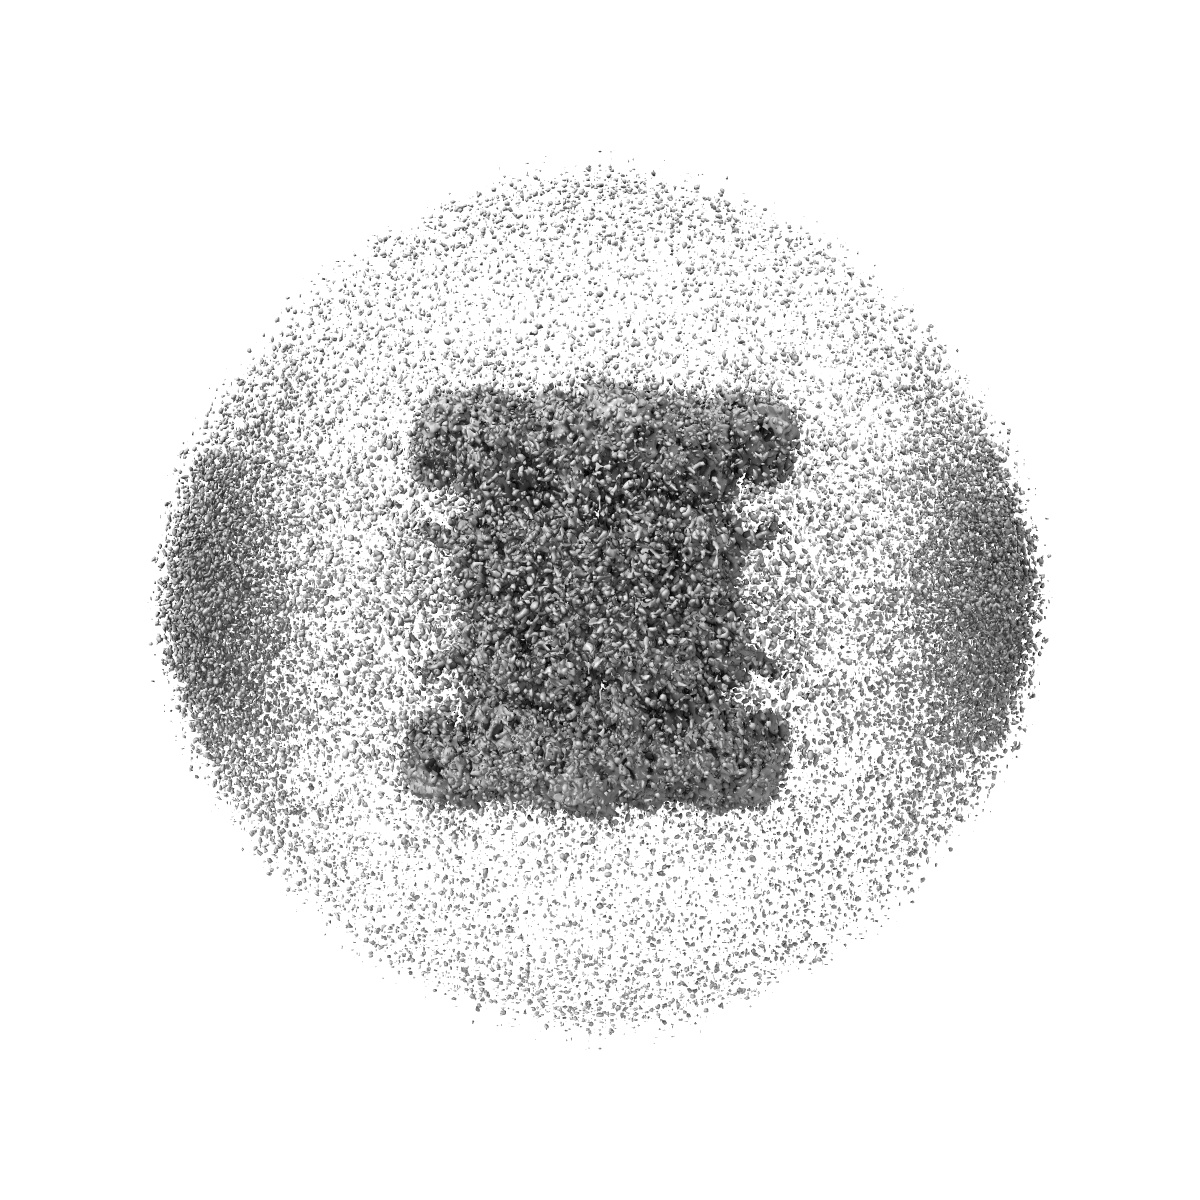

Human p97/VCP structure with a triazole inhibitor (NSC799462/dodecamer)

Single-particle3.33 Å

Sample: p97/VCP AAA+ ATPase/NSC799462

Mechanism of allosteric inhibition of human p97/VCP ATPase and its disease mutant by triazole inhibitors.

(2024) Commun Chem , 7 , 177 - 177